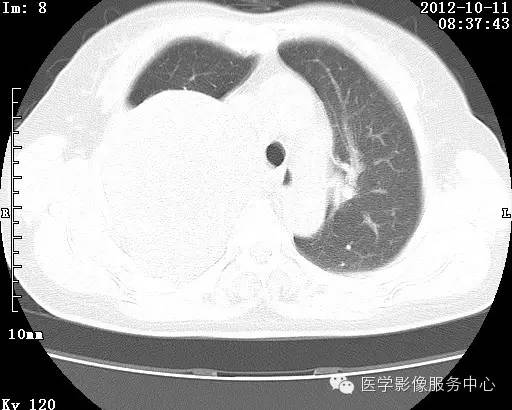

【病例】右肺巨大错构瘤1例CT影像表现

病史:女 65岁咳嗽咳痰 右肺巨大肿块就诊。

错构瘤的主要组织成分包括软骨、脂肪、平滑肌、腺体、上皮细胞,有时还有骨组织或钙化。错构瘤一般为实质致密的球形、卵圆形,也可以是分叶状或结节状,大多数直径在3cm以下。

错构瘤的发病年龄多数在40岁以上,男性多于女性。 绝大多数错构瘤(约80%以上)生长在肺的周边部,紧贴于肺的脏层胸膜之下,有时突出于肺表面。其特征钙化为爆米花样钙化,内有脂肪软骨成分等等。最常见的部位是胸膜下肺实质内,其次为主支气管或肺叶、肺段支气管内。

瘤内出现“爆米花样钙化”是诊断的主要指标之一。早期的点状、斑片状及结节状钙化 随时间增加钙化数量及范围会增加,最终可能演变 为爆米花样钙化;

另一项主要指标是瘤测得脂肪成分是诊断错构瘤。